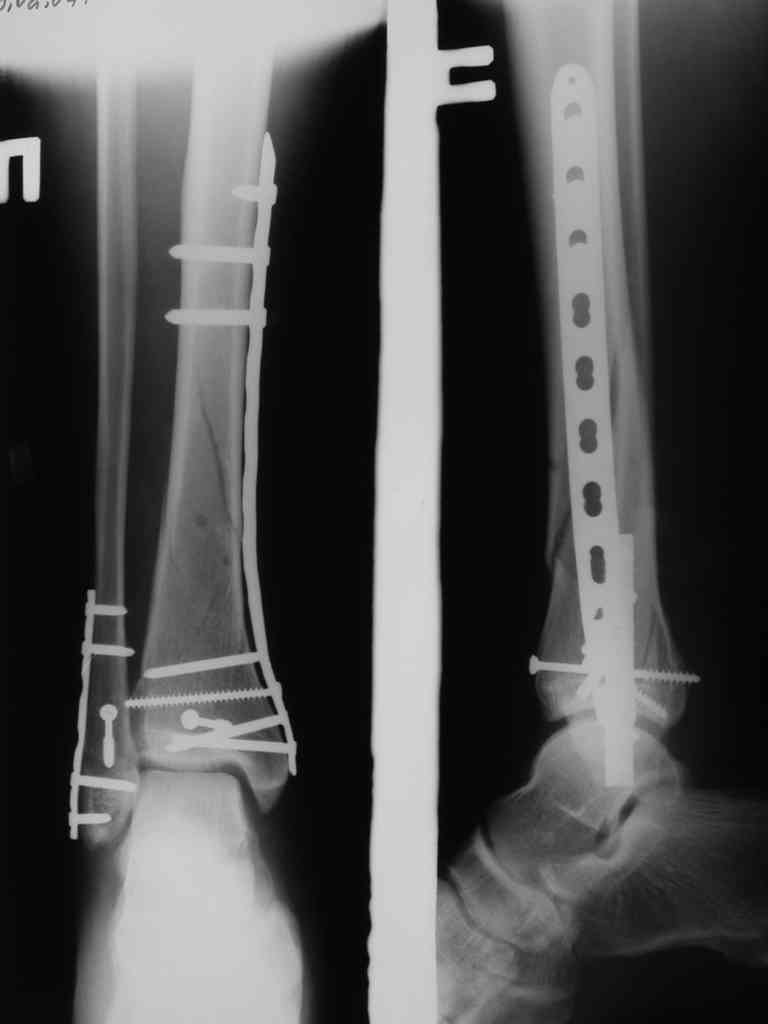

Сегодня прооперировали. Длительность 4-50. Начали как и говорил сверху вниз линейным разрезом - фиксация задне-латерального отломка к проксимальному 2мя винтами, затем "прилепили" к ним передне-медиальный (пришлось повозиться - была интерпозиция и довольно "сложный" винт) - к проксимальному 1 винтом и к задне-латеральному 1 винтом.Кстати на фото видно - у передне-медиального отломка еще осколок в области сустава, несколько смят. Далее началось веселье - второй доступ - задне-наружный к латеральной лодыжке и заднему краю, но оказалось, что задний край больше задне-медиальный (по снимкам было непонятно). Плюс к этому репозиция его мягко говоря сложновата (больной на спине, стол низкий и не поднимается). В общем выставили, фискировали 2мя винтами, на ЭОПе вроде стал, только верх отошел. Латеральную лодыжку заведующий решил интрамедуллярно (не хотел еще винты толкать), сначала 3мм спицей - нестабильно, затем 4мм стержень (не помню по автору) - ОК (кстати в месте перелома мелкая крошка - дефект до 5х7 мм по кортикалу). Ну медиальная лодыжка стандартно - третий разрез - винт 3,5 мм. Визуально все стабильно. На Р-контроле - видна небольшая ступенька заднего края по одному из контуров.

Рентгенограммы

Мы бы фиксировали пластиной м/берцовую кость открыто, на б/берцовую пластину MIPO, при необходимости сустав открыть минимально.

На фото простой суставной, метафиз. оскольчатый с переходом на диафиз перелом, пластина MIPO.